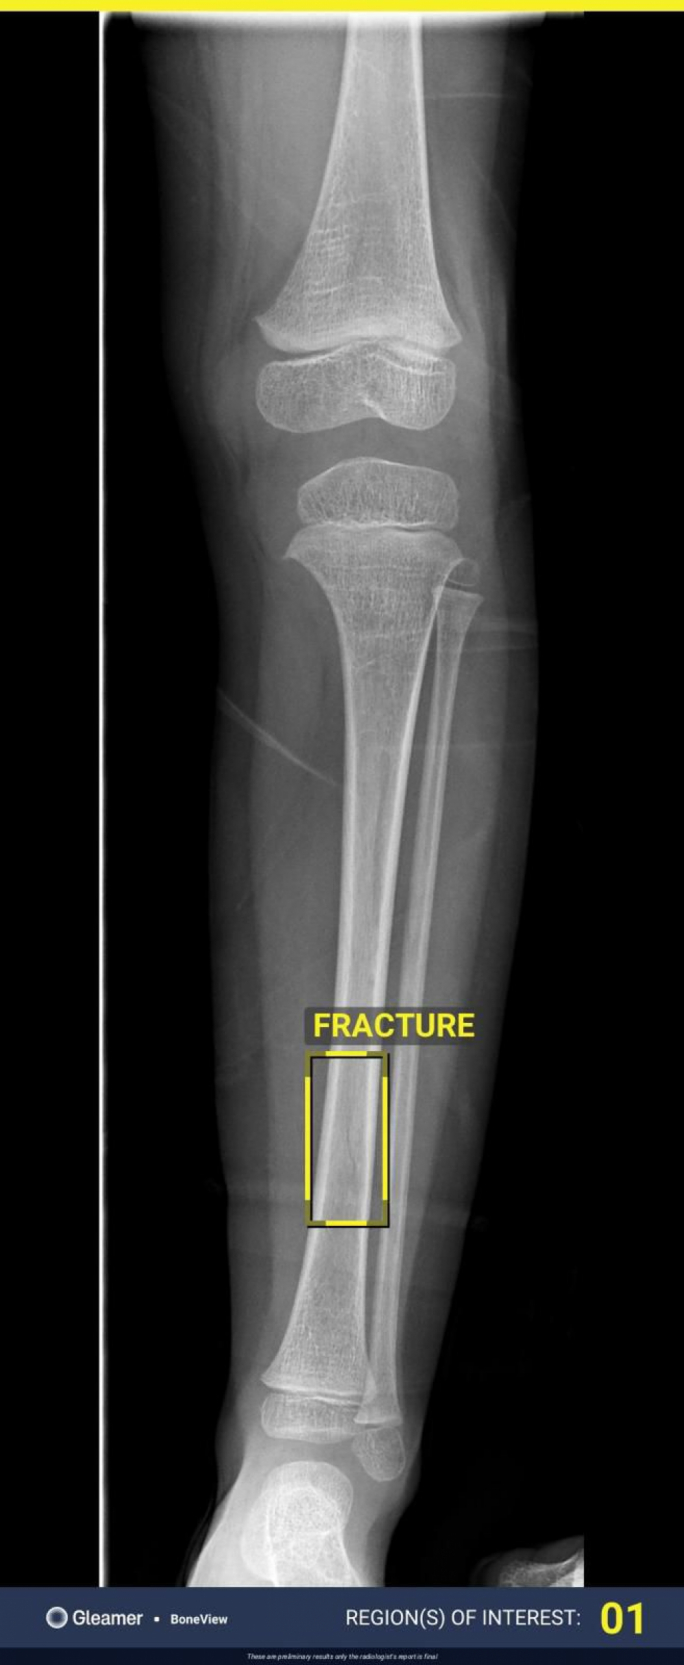

Hi tkellmet fuq l-agħar kwistjoni, meta waqt żmien il-Milied, it-tifla ġiet id-dar b’differenza fl-imġiba u hi għalqet għajn waħda għax ħasbet li din l-imġiba setgħet kienet sforz il-kundizzjoni tagħha. Madankollu, hi ndunat li t-tifla tagħha ma setgħetx tqum bilwieqfa fuq saqajha, u bdiet tilwi waħda minnhom. Meta ħadet X-Ray ta’ sieq it-tifla, indunat li kien hemm ksur f’għadma ta’ sieqha. “It-tabib kien sorpriż għax ma kellha l-ebda tbenġil, allura qalli li t-tifla ma qalgħetx daqqiet imma probabbli lwiet sieqha,” hi rrakkontat.